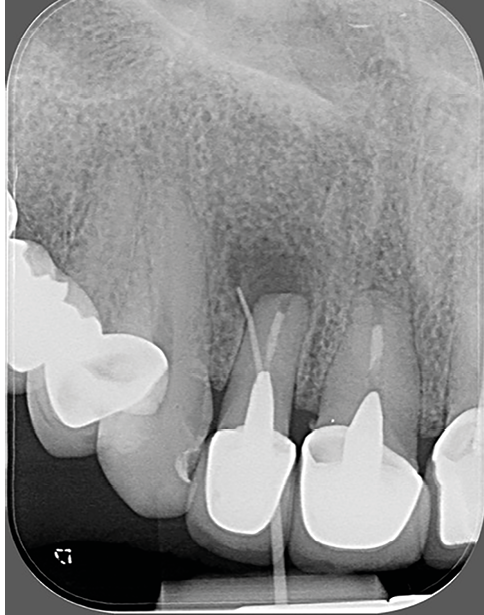

- un retraitement ne parviendrait pas à gérer une situation iatrogène : par exemple, une lésion accompagnée d’une importante extrusion de matériau d’obturation (fig. 3a-b).